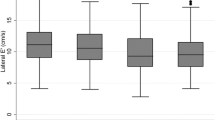

Age dependence of diastolic function differentiates normal function from dysfunction

Myocardial velocity measurements by tissue Doppler imaging clearly demonstrate the predominant influence of ageing on diastolic function [68, 69], confirming previous reports using different imaging techniques. There is a steep and linear decline of normal early diastolic velocity with ageing in normal people, from 16 cm/s at the age of 20 years to 6 cm/s at 80 years. This decline equals a decrease of 0.16 cm/s (i.e. 1% of the original value) every year. Accordingly, cut-off values for normality vs dysfunction should be defined in a linear regression equation as a function of age [19]. Using pulsed tissue Doppler imaging, the cut-off level for normal age-related velocity is calculated as −0.15 × age (years) + 18 (cm/s). This approach allows individual patients to be assigned to normality or dysfunction/risk and avoids the inconsistencies arising from normal values defined for different age groups. There are no sex-related differences in the association of diastolic function and age. E′ is also useful in the detection of impaired left ventricular relaxation and estimation of filling pressure (E/E′) in patients with atrial fibrillation [70].